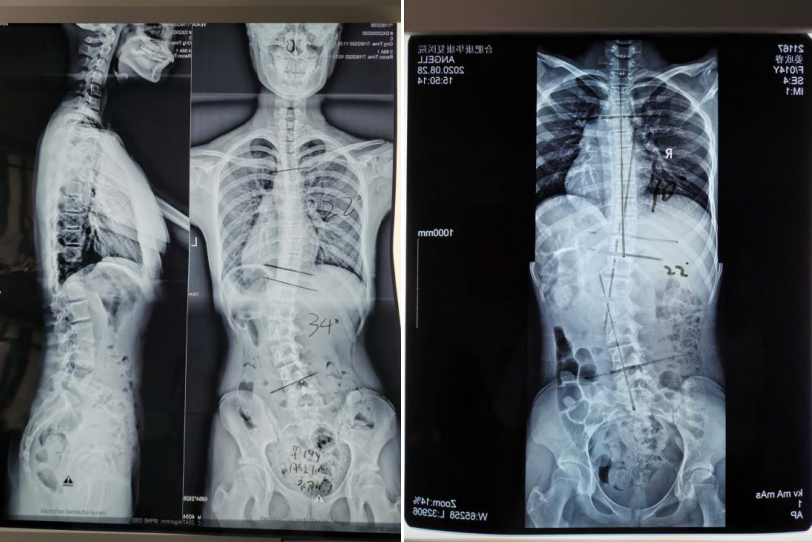

加速康复骨科李副院长和中西医结合康复科专家高主任联合会诊,确诊睿睿为青少年特发性脊柱侧弯(胸椎22°/腰椎34°),考虑到手术风险性,康复科团队为她制定了详细的中西医康复治疗方案。

2020.7.18治疗前X片 2020.8.28治疗后X片

经过一个月的强化康复治疗和训练,睿睿的脊柱侧弯已经明显恢复正常(胸椎10°/腰椎22°),双肩基本平高,腰椎活动度基本正常,双侧髂脊基本对称。不爱说话的她也随着病情的好转变得开朗了,重新找回属于自己的快乐生活。